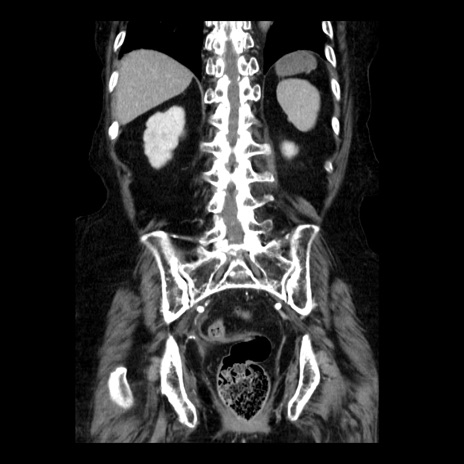

症例14(冠状断像)

【症例】 90歳代女性

【主訴】 腹痛・嘔吐

【現病歴】今朝から左側腹部痛を認めた。 経過観察していたが、嘔吐を認めたため来院。

【既往歴】 子宮癌術後

【身体所見】 意識清明、BP 127/54mmHg、P 98bpm Sp02 95%(RA)、BT 35.8°C、腹部平坦・軟腸ぜん動音聴取良好、右下腹部圧痛(+) 反跳痛なし

【データ】WBC 9800、CRP 0.46